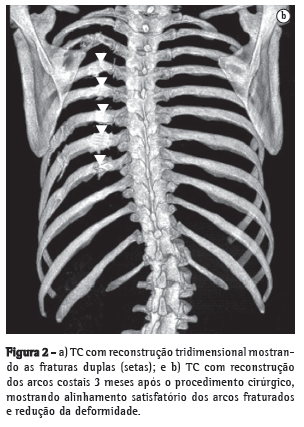

Paciente do sexo feminino, 32 anos, vítima de acidente automobilístico, que ocasionou hemopneumotórax esquerdo, contusão pulmonar esquerda e fraturas duplas do terceiro ao oitavo arcos costais esquerdos, evidenciados na radiografia e tomografias computadorizadas (TC) do tórax (Figuras 1 e 2). As tomografias de crânio, coluna cervical, abdômen e pelve apresentaram-se normais, assim como eletrocardiograma, ecocardiograma, enzimas musculares e marcadores de necrose miocárdica. Foi realizada drenagem torácica fechada em selo d'água e solicitada a instalação de cateter epidural para analgesia contínua com bomba de infusão. A paciente apresentava deformidade torácica importante e dor, apesar de doses elevadas de analgésicos. Antecipou-se que o quadro, se não tratado cirurgicamente, evoluiria para deformidade complexa da parede, com possível acometimento da respiração. Não necessitou de ventilação mecânica. Em vista desse quadro clínico, foi decidido o tratamento cirúrgico para estabilização das fraturas. O procedimento foi realizado por toracotomia póstero-lateral esquerda. Foram encontradas fraturas duplas do terceiro ao oitavo arcos costais esquerdos com ruptura completa de vários pedículos intercostais, herniação e impactação do segmento fraturado (6 arcos) para o interior da cavidade pleural, com compressão importante do parênquima pulmonar (toracoplastia traumática). Foi realizada redução das fraturas e fixação das costelas com fios de aço número 5, perfurando as extremidades das costelas com broca número 2, passando-se o fio de um segmento de costela para outro e amarrando-se o fio de aço. Foi colocado um dreno de tórax, que foi retirado no terceiro dia. A paciente evoluiu com excelente controle da dor e melhora na dinâmica ventilatória. A radiografia e a tomografia no pós-operatório confirmam o bom resultado do tratamento cirúrgico. (Figura 3).